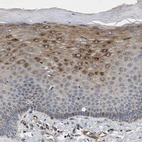

Immunohistochemical staining of human skeletal muscle strong granular cytoplasmic positivity in myocytes.